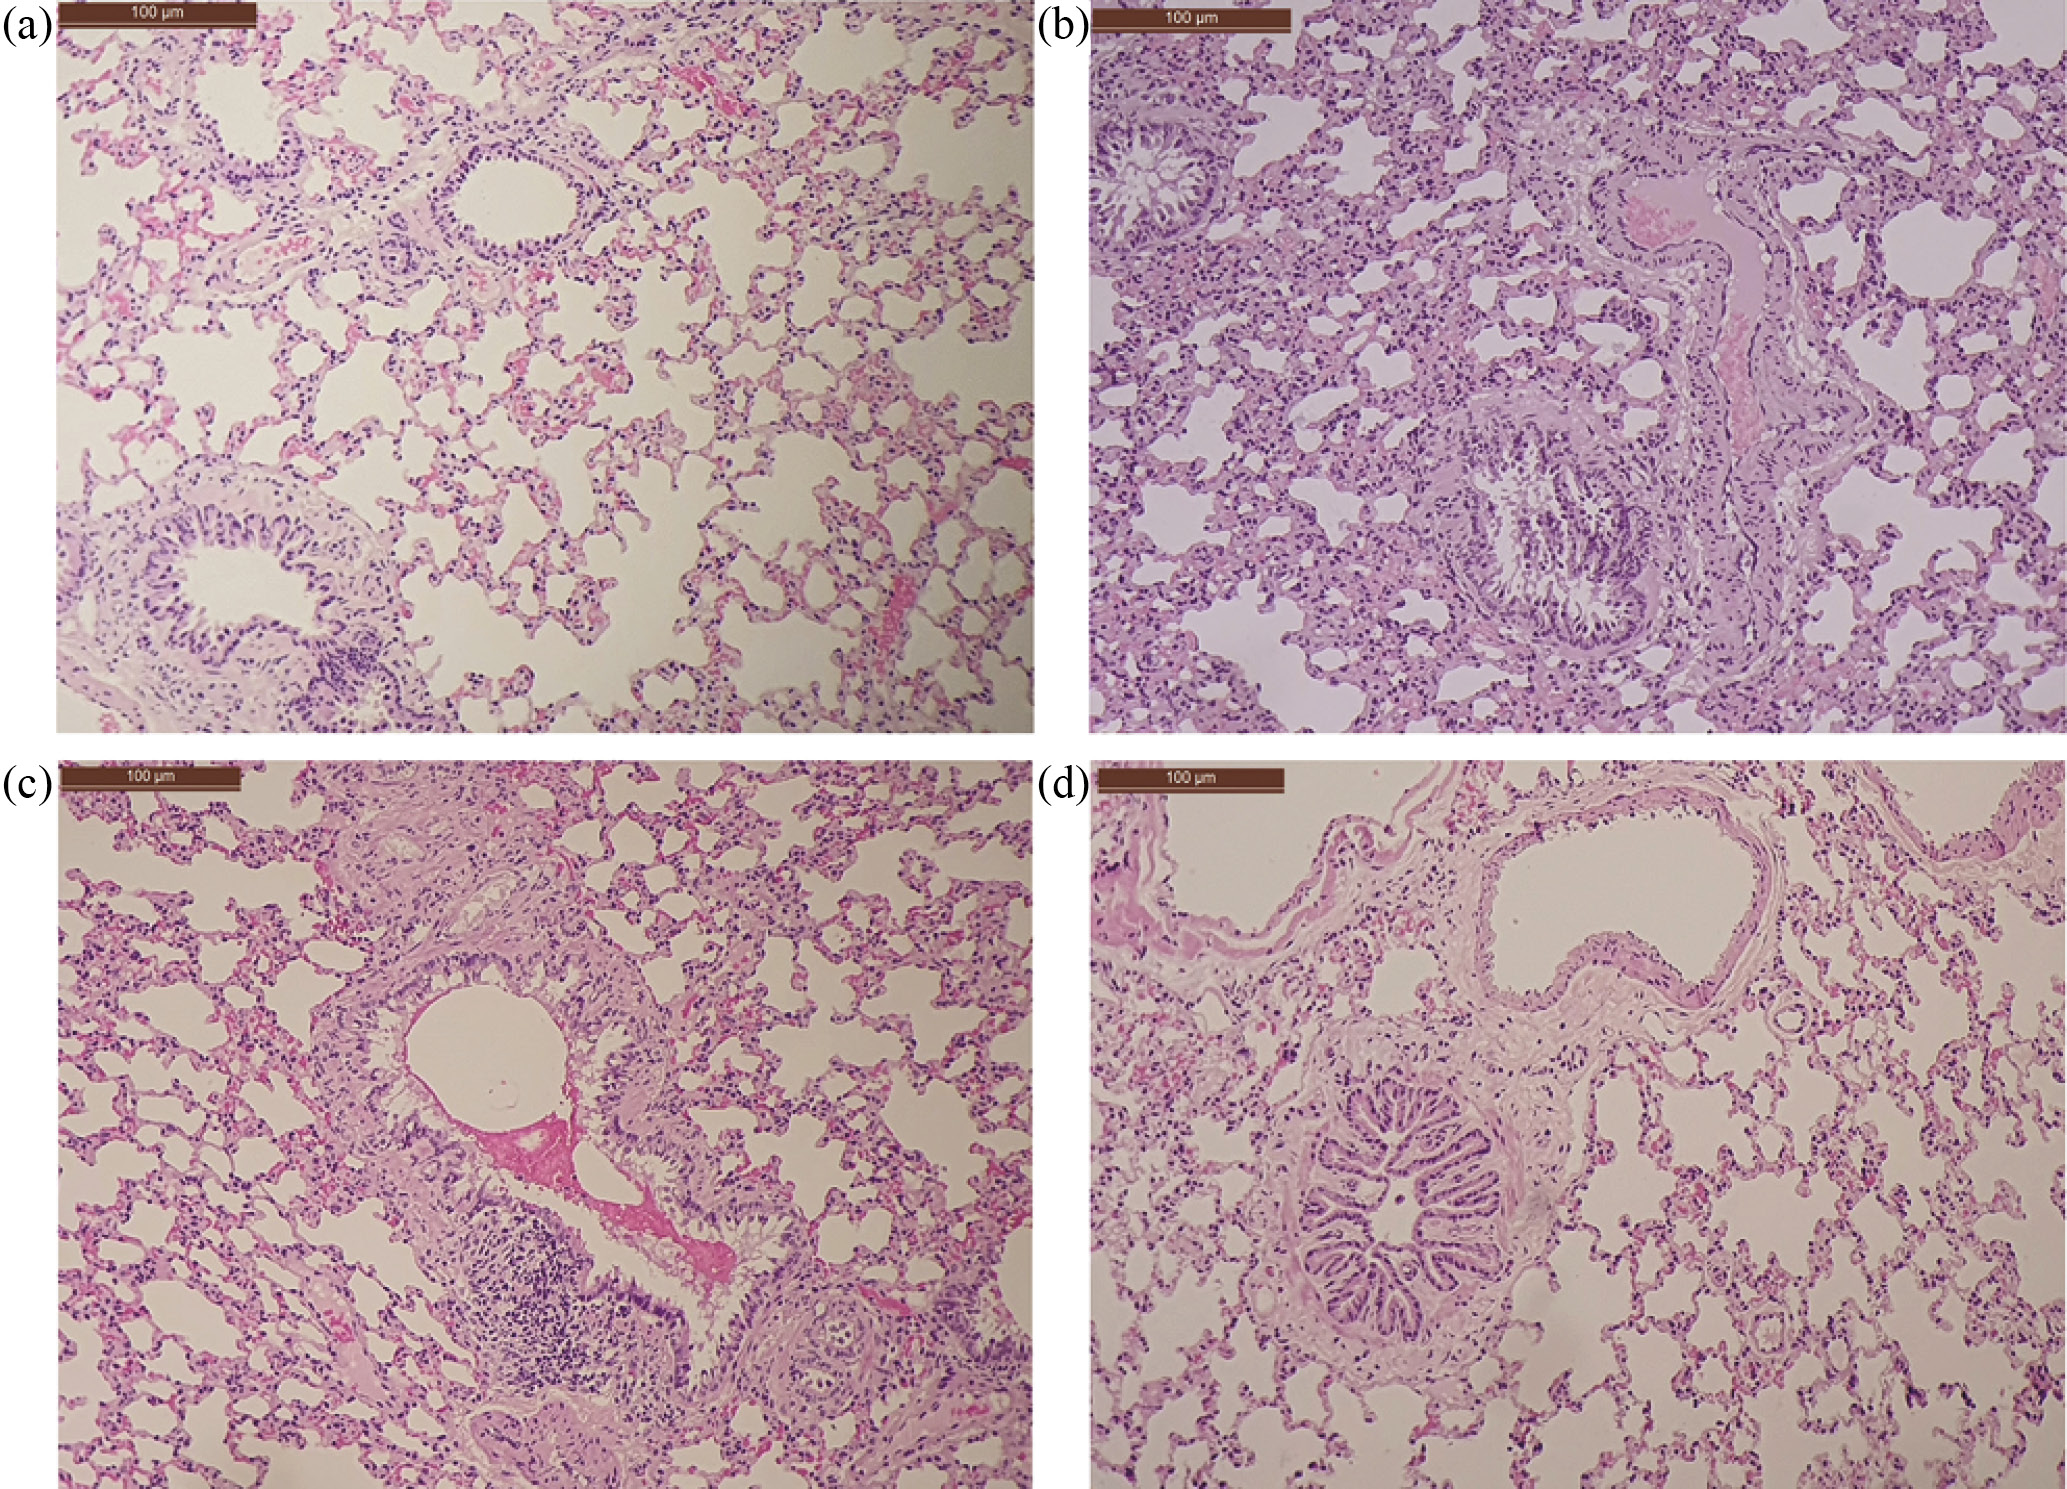

В легких группы животных ДОКС отмечался слабо и умеренно выраженный катаральный бронхит с экссудацией слизисто-белковых масс в просвет и десквамацией клеток эпителия. Альвеолярная ткань в большинстве случаев сохраняла воздушность, однако встречались нерегулярные зоны дислектаза и умеренно и ярко-выраженное полнокровие с явлениями стаза в эктазированных сосудах мелкого калибра. Отмечалась интерстициальная и перибронхиальная слабовыраженная лимфо-гистиоцитарная инфильтрация. Вокруг сосудов и бронхов определялись отложения коллагеновых волокон от умеренного до ярко выраженного, также выявлялись дистрофические изменения мышечных слоев стенки сосудов (рис. 5). Толщина межальвеолярных перегородок в образцах ДОКС группы была больше, чем в контроле, а процент свободного альвеолярного пространства снижался (рис. 6). В большей степени это связано с отеком, полнокровием капилляров и интерстициальной инфильтрацией, но может быть связано и с пролиферацией стромального компонента легких. При окраске по Маллори в тканях легкого в зоне альвеол отмечалось увеличение процента коллагеновых волокон (интерстициальный фиброз слабой степени выраженности) (рис. 7). Все описанные повреждения свидетельствуют о значительном повреждающем действии ДОКС на ткани легких.

Рис. 5. Репрезентативные фотографии легких животных экспериментальных групп. Разный диаметр альвеол, толщина альвеолярных перегородок, интерстициальная инфильтрация легкого. (a) – контроль; (b) – ДОКС; (c) – НР+ДОКС; (d) – НР/НР+ДОКС. Окраска гематоксилином-эозином, ×100.

В группах животных НР+ДОКС и НР/НР+ДОКС также отмечались морфологические паттерны – бронхит, фиброз и интерстициальная воспалительная инфильтрация, как и в группе ДОКС, однако эти параметры статистически достоверно менее выражены в группе НР/НР+ДОКС. Альвеолярная ткань более воздушная в группах НР+ДОКС и НР/НР+ДОКС, толщина межальвеолярных перегородок приближена к значениям контрольной группы (p < 0.05). В табл. 4 представлены данные со средними баллами на группу по морфологическим параметрам.

По результатам статистического анализа в группе НР/НР+ДОКС показано статистически значимое изменение всех параметров при сравнении с группой ДОКС. В группе НР+ДОКС отмечено статистически достоверное увеличение% альвеолярного пространства.

Таким образом, внутривенное введение НР в превентивном режиме оказывает более выраженное протективное действие в отношении легких при проведении включающей ДОКС химиотерапии.